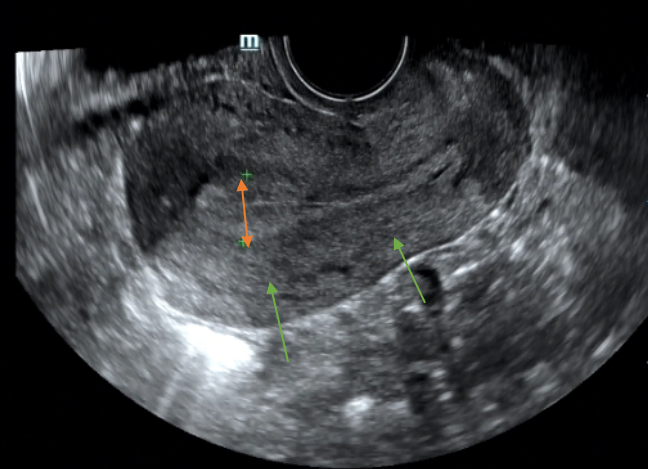

在超声检查中,正常情况下,子宫内膜的回声是均匀的,子宫内膜在超声图像中通常表现为宫腔内的条状或线状回声。

然而,当子宫内膜出现病变或异常时,回声就会变得不均匀,出现增厚、斑驳、不规则等表现,这是一种超声描述性语言,而非疾病的诊断。这种不均匀的回声可能提示子宫内膜存在一些潜在的问题,但也可能只是正常的偶发超声异常,需要进一步的检查和评估。

宫腔镜是诊断宫腔粘连的金标准。超声检查虽然不能确诊宫腔粘连,但是也是初步评估宫腔粘连的重要手段。

超声检查中,增生的子宫内膜可能表现为回声不均匀或局部增厚。子宫内膜增生的高发年龄段以围绝经期以及绝经期女性为主,处在该年龄段的女性以及有高危因素的女性朋友,尤其当合并异常的阴道出血时,我们应该警惕该疾病可能。

而当绝经后女性的单层子宫内膜厚度超过4mm时,更需警惕子宫内膜癌的可能,尤其是伴有肥胖、未对抗的雌激素使用、多囊卵巢综合征、2型糖尿病等高危因素的患者。超声检查中,子宫内膜癌可能表现为回声不均匀、形态不规则或局部明显增厚。